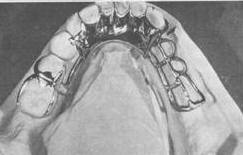

| Barra lingual

Este es el más utilizado.

Se debe utilizar siempre que sea

posible a menos que existan ventajas que pueden obtenerse de

otro conector.

Tales

situaciones son poco comunes.

-

Forma :

-

Plana en el lado del tejido

-

Convexo o de lágrima en el lado de la lengua

(forma de sección de 1 / 2 pera, con el borde delgado hacia los

dientes)

- Tamaño:

-

Ancho ocluso-gingival = 4 a 6 mm.

-

Espesor = l, 5 a 2 mm.

- Posición:

-

El borde inferior debe ser tan bajo como el frenillo

lingual y y el piso de boca (con la lengua en

protrusión lo permita) Para

ello debe observar el movimiento de la lengua.

-

El

borde superior debe ser l, 5-2.0 mm o más por debajo del

margen gingival.

Por razones de higiene el borde superior de la barra

lingual, todavía debe

mantenerse lo más lejos de

el margen gingival como sea posible.

-

En

caso de extensión distal habrá algún movimiento de la

barra lingual que barra los tejidos blandos Ver

imagen inferior izquierda. Si la

reabsorción ósea se acelera esto hará que la barra

lingual se impacte en el piso de boca ó en la mucosa

lingual de los diente antero-inferiores

Para eliminar la barra lingual de afectar

los tejidos blandos, un separador de cera (alivio) de

un espesor de cera de calibre 30 se coloca en el modelo

de trabajo Ver imagen inferior derecha., para

luego ser reproducido

en material refractario